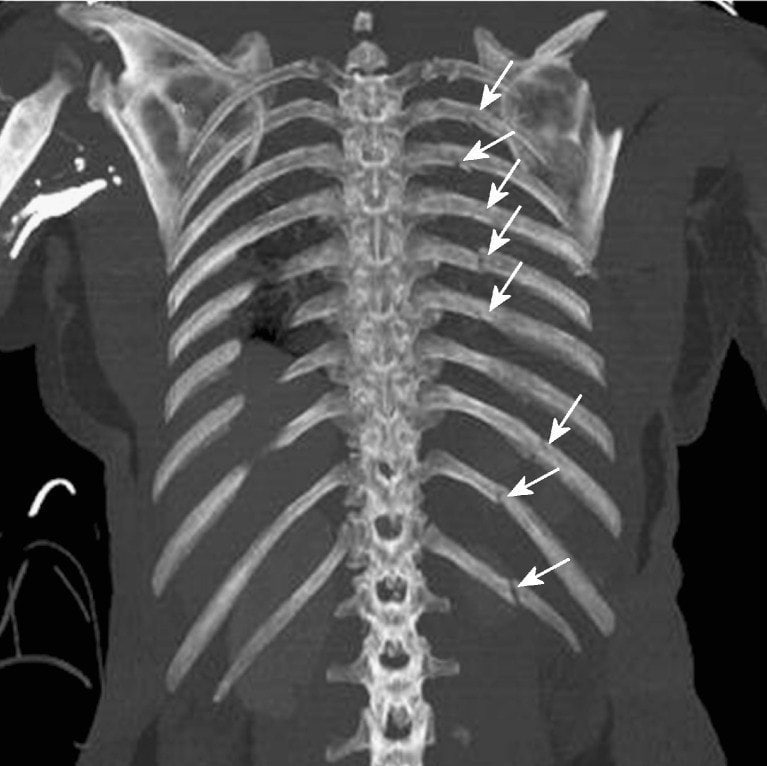

Травма 10 ребра

Травма 10 ребра 112 фотографий